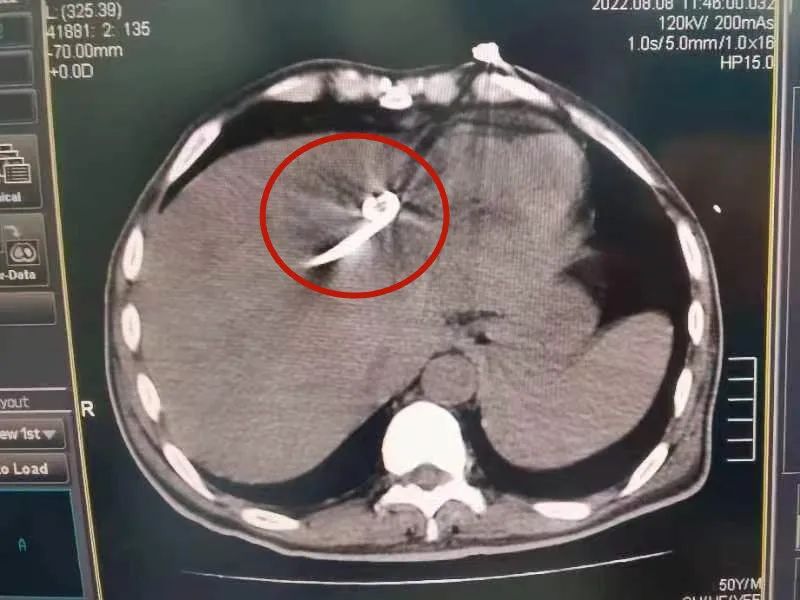

近日,另一位中年男性HIV患者,因“腹胀伴呃逆“行腹部彩超,发现肝脏占位,腹部增强CT提示肝左叶75*93mm病灶,可见分隔,且中央为液性密度,增强扫描显示边缘及分隔强化,结合白细胞升高的实验室检查结果,诊断为肝脓肿。患者收治于呼市二院肝病重症医学科,挂职副院长袁春旺床旁查看患者并结合其增强CT及实验室检查结果,分析认为患者HIV感染合并肝脓肿诊断成立,CD4细胞明显降低,免疫功能缺陷,单靠抗生素治疗很难达到脓肿吸收的理想效果,脓肿大部分液化坏死,需要行脓肿引流。

8月8日上午,袁春旺带领该院介入团队为患者行CT引导肝脓肿经皮穿刺引流术,手术历时10分钟,成功置入一根10.2F引流管,并同时抽出脓液150ml。